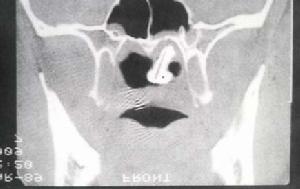

1.對中耳乳突炎,尤其合併有膽脂瘤和骨破壞時,可明確其範圍、程度,以提供手術方案。

2.可明確良、惡性腫瘤的形態、大小、範圍、鄰近器官的侵犯與轉移等,對某些腫瘤可作出定性診斷。

5.耳部先天性疾病,尤其中耳及內耳的先天性畸形,CT有助於確診。